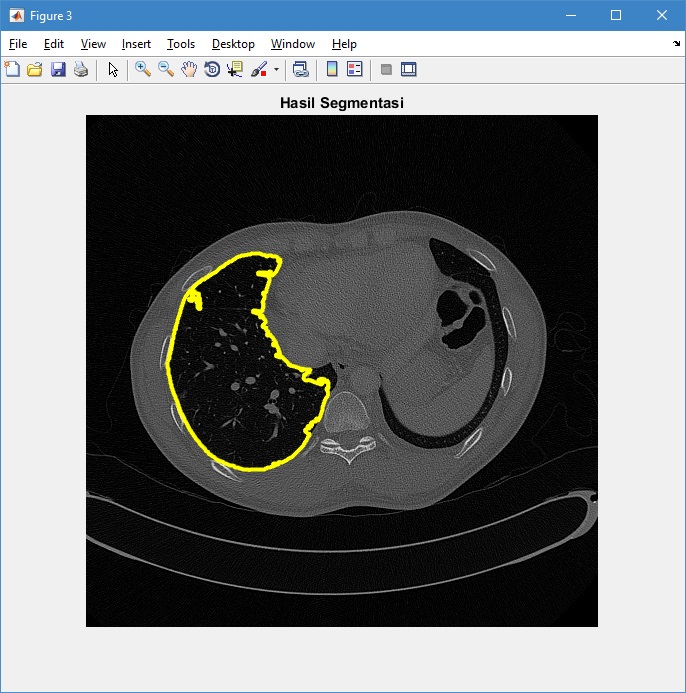

4. Menampilkan citra hasil segmentasi

figure, imshow(Img,[])

title('Hasil Segmentasi')

axis off

hold on

[c,~] = bwboundaries(bw,'noholes');

for k = 1:length(c)

boundary = c{k};

plot(boundary(:,2), boundary(:,1),'y','LineWidth',3)

end

hold off